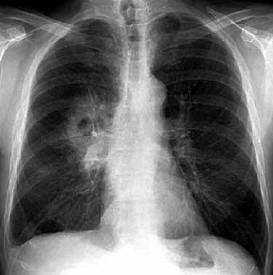

Considerando um homem de 51 anos com a radiografia de tórax mostrada a seguir, é correto afirmar que

(Arquivo pessoal; imagem usada com autorização)